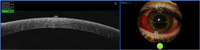

La córnea posee cinco capas histológicamente bien diferenciadas de superficie a profundidad: epitelio, membrana de Bowman, estroma, membrana de Descemet (MD) y endotelio. Las capas de mayor reflectividad en la OCT corresponden a la superficie anterior corneal y al límite posterior de la córnea con la cámara anterior

1. Se puedenobservar corneas sanas (distinguimos epitelio, estroma y endotelio) (

Figura 1). También se pueden estudiar adelgazamientos corneales como el queratocono (

Figura 1. OCT corneal normal.